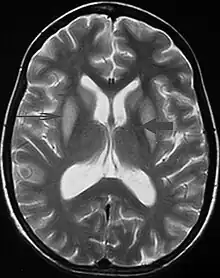

Axial fat-saturated T2-weighted image showing hyperintensity in the pons with sparing of the peripheral fibers, the patient was an alcoholic admitted with a serum Na of 101 treated with hypertonic saline, he was left with quadriparesis, dysarthria, and altered mental status | |

It can be diagnosed clinically in the appropriate context, but may be difficult to confirm radiologically using conventional imaging techniques. Changes are more prominent on MRI than on CT, but often take days or weeks after acute symptom onset to develop. Imaging by MRI typically demonstrates areas of hyperintensity on T2-weighted images.[29]